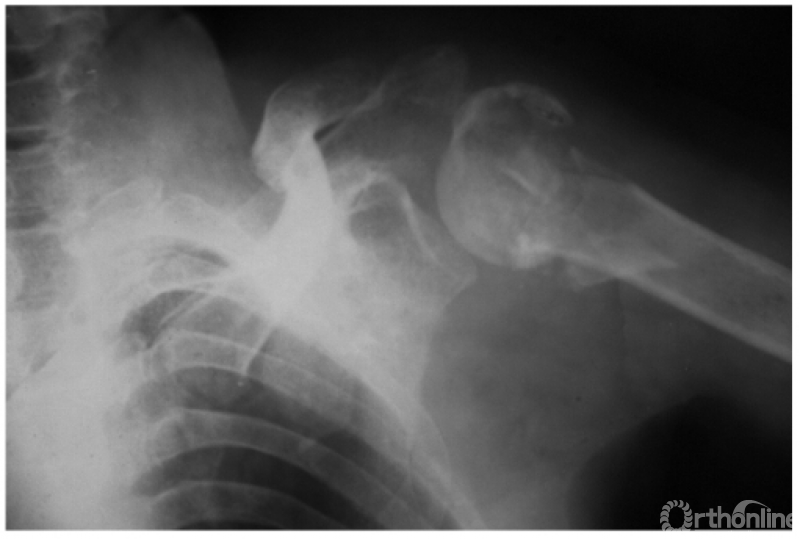

例5:肩关节喙突下脱位并外科颈劈裂骨折及同侧锁骨中断骨折(如下图)。